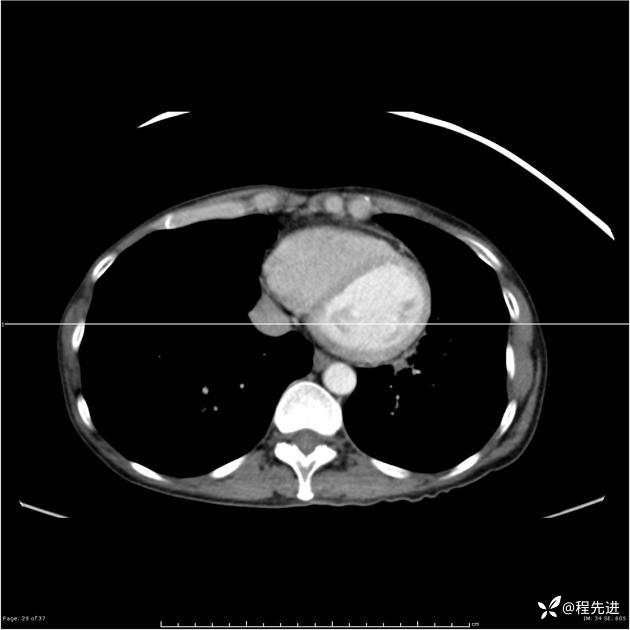

病例女,53岁,气管、左主支气管、下叶支气管内结节,乳头状瘤?期待你的精彩解读

女,53岁

乳头状瘤?